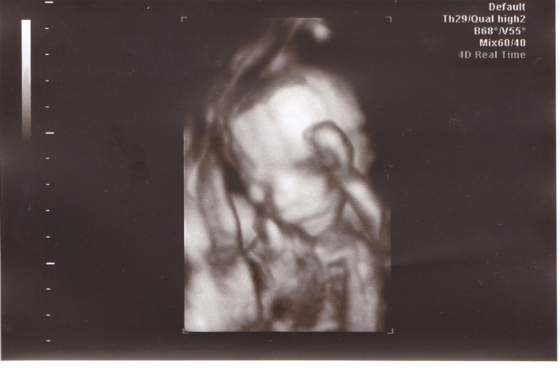

Witam. Więc i ja sie pochwalę wczorajszym usg ( miałam drugie prenatalne)

W skrócie wszystko ok, waży aż 417g. (21 tydzień i 4 dzień)

Obraz 001.jpg pod koniec w opisie mam zapis- Płeć- prawidłowe męskie narządy płciowe :tak:

więc potwierdzony ogonek po raz czwarty, mogę robić zakupy :-)